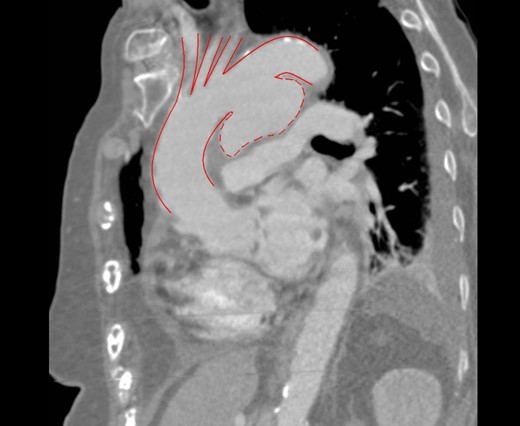

The patient remained on IV antibiotics while treatment was planned. An interval CT was performed 42 days after her initial diagnosis which showed that the aneurysm had significantly increased in size measuring up to 5.5 cm (Fig. 1 ).

The decision was made to perform a hybrid procedure involving endovascular repair of the aneurysm and extra-anatomical bypass of the supra-aortic vessels with a right-to-left common carotid crossover bypass and a left common carotid to left subclavian bypass to protect the cerebral and left subclavian blood flow (Fig. 2). This was performed 46 days after admission. The patient was admitted to the ICU for 24 h post procedure and discharged from the hospital on the 25th postoperative day.

3D reconstructed CT scan showing the endovascular aortic arch repair.